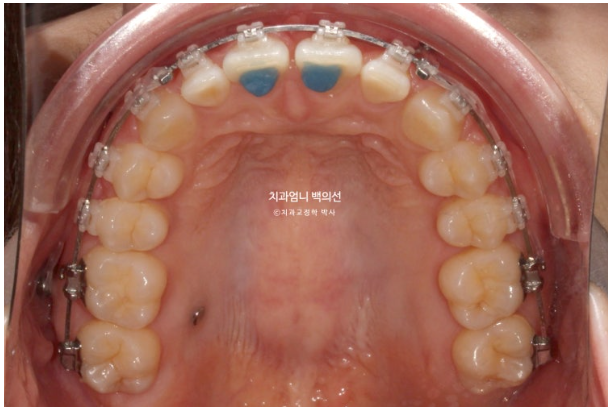

미니스크류를 사용했고

24.02

과개교합 해소를 위해 앞니에 바이트블럭도 붙였습니다.